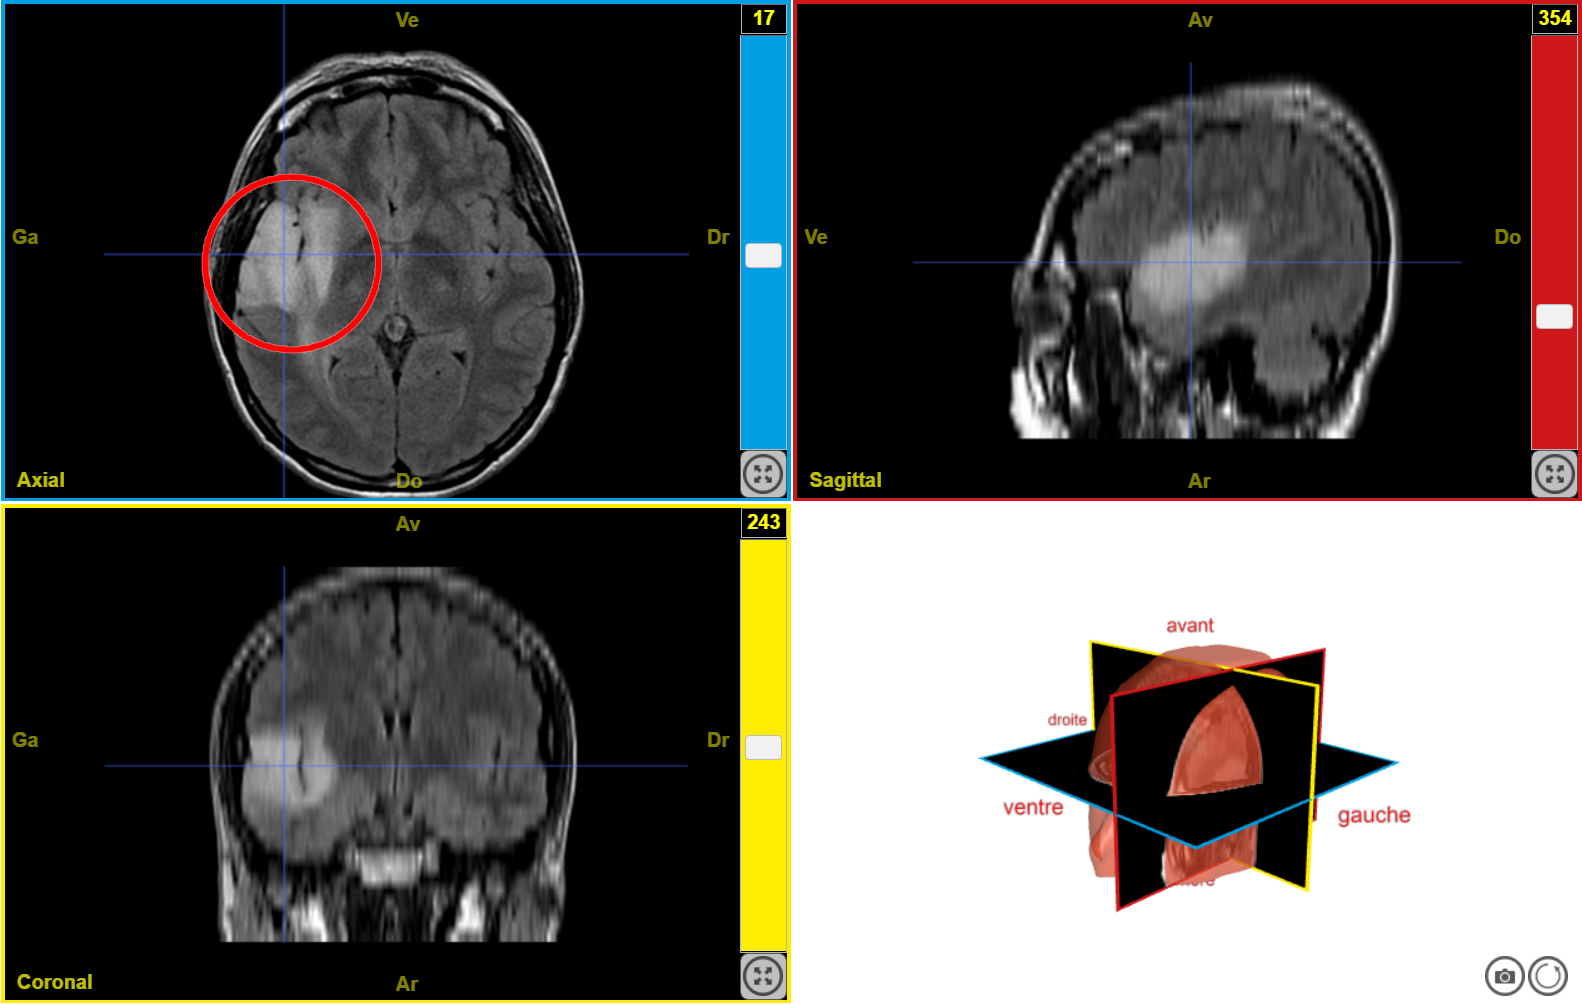

IRM tumeur T2 n2